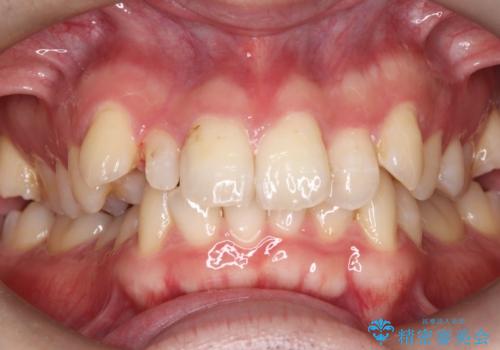

- 20代男性

- 主訴:右上の前歯が何しなくても痛い

右上2番の歯に自発痛を認め、症状や歯髄診・レントゲン像から不可逆性歯髄炎と診断し、精密根管治療から歯冠補綴まで行うこととなりました。

初診時に歯髄診断を行い、不可逆性歯髄炎と診断し抜髄から補綴修復までの流れを説明し、精密根管治療、ファイバ-コア築造、オールセラミッククラウン(St)修復を行うこととしました。